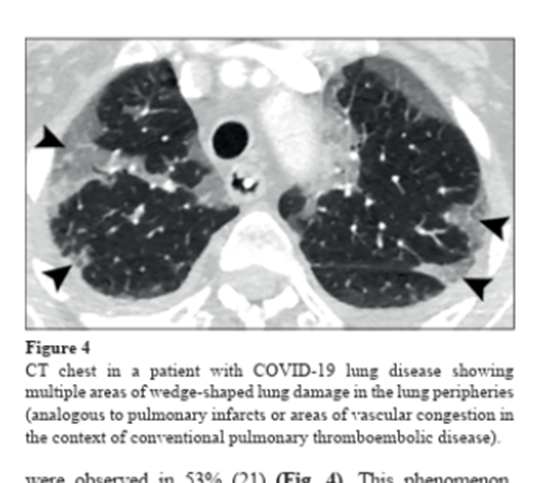

The areas of lung damage looked like what we see when someone has blood clots in the lungs.

5/25 bit.ly/4j6fIpxImage

The pattern of lung disease we saw on medical imaging in people with #COVID-19 tells us that the disease is NOT pneumonia, it is a vasculopathy (disease of blood vessels).